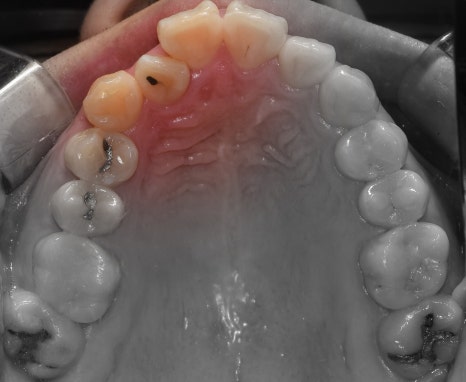

측면에서는 크게 2가지를 느낄 수 있습니다.

- 전치부 치아들의 치축, 전방 뻐드러짐

- 1치대 1치의 관계

*정상이라면, 1치대 2치의 관계를 가져야 됩니다.

또한, 측절치 및 송곳니의 총생들도 같이

관찰을 할 수 있습니다.

앞서, 1치대 1치 관계에 있던 교합관계들이

1치대 2치의 관계로 바뀐것을 볼 수 있으면서

길쭉하게 느껴졌던, U shape 형태의 악궁이

딱 보기 좋은, U shape 로 바뀌었죠.